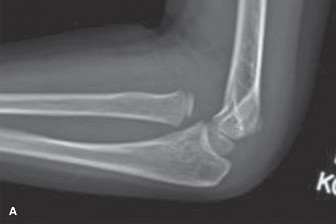

Displaced Supracondylar Humerus Fracture

- Radiographic Findings: AP and lateral radiographs of the left elbow revealed a significantly displaced supracondylar humerus fracture. On the lateral view, the anterior humeral line passed anterior to the capitellum, and Baumann's angle was significantly decreased (less than 45 degrees), indicating severe extension-type displacement with posterior and medial angulation of the distal fragment relative to the proximal shaft. The fracture line was oblique, originating from the olecranon fossa posteriorly and extending anteriorly through the coronoid fossa.

- Classification: Gartland Type III supracondylar humerus fracture (completely displaced). Given the neurovascular compromise (absent radial pulse), this also qualifies as a pulseless supracondylar fracture.

- Decision: Urgent closed reduction and percutaneous pinning (CRPP) followed by a long arm cast.

- Classification: Gartland Type III (completely displaced) with neurovascular compromise (absent radial pulse).

- Rationale: Gartland Type III supracondylar fractures are unstable and carry a high risk of neurovascular injury and compartment syndrome. The presence of a pulseless limb, even if initially warm and well-perfused (pink pulseless hand), mandates immediate reduction to restore perfusion. If pulse does not return after closed reduction, further intervention such as open reduction and exploration of the brachial artery may be necessary. Definitive surgical fixation with K-wires provides stable immobilization, allowing for early pain control and preventing further displacement or complications.